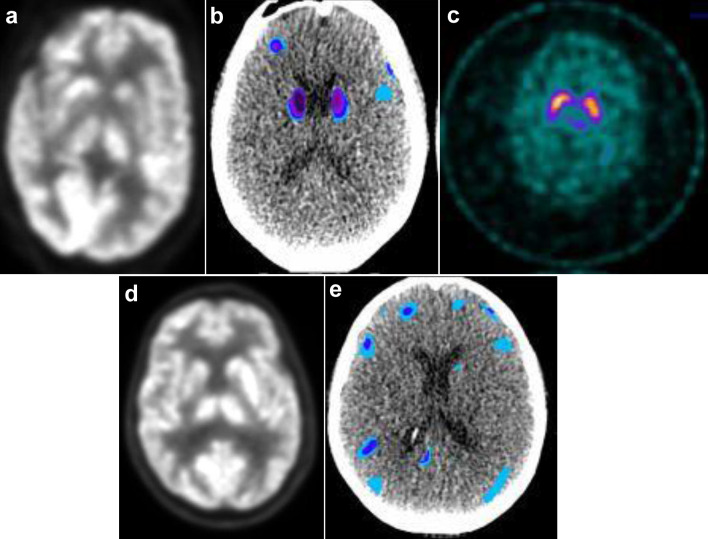

After ciltacabtagene autoleucel (cilta-cel) in multiple myeloma, 5% of patients can develop parkinsonism, with a high fatality rate. The pathogenesis and optimal therapy of parkinsonism from B-cell maturation antigen chimeric antigen receptor T-cell (CAR T-cell) therapy are unknown. Parkinson's disease occurs from the loss of dopaminergic neurons in the substantia nigra. However, in cilta-cel-associated parkinsonism, dopamine transporter imaging is normal, rendering traditional agents such as carbidopa/levodopa ineffective. Thus, the pathogenesis of cilta-cel-associated parkinsonism and Parkinson's disease is distinct. As CAR T-cell therapy for multiple myeloma is expanding and moving to earlier lines, the need to optimize therapy for parkinsonism, a potentially life-threatening complication, becomes more urgent. This report presents the first documented cases of two patients with immune effector cell-associated hemophagocytic lymphohistiocytosis-like syndrome and cilta-cel-associated parkinsonism, effectively treated with ruxolitinib.

Abstract Image